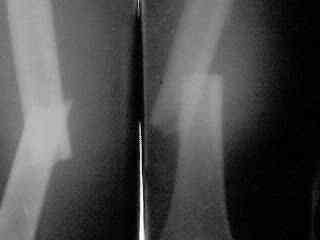

Еще вариант - ввести традиционный 4-гранный, кюнчеровский, или какой есть гвоздь помощнее (можно и антеградно, но хоть даже и открыто ретроградно, традиционно со стороны перелома), а со стороны надмыщелков заклинить его одним или двумя плоскими стержнями. Пример в приложении.